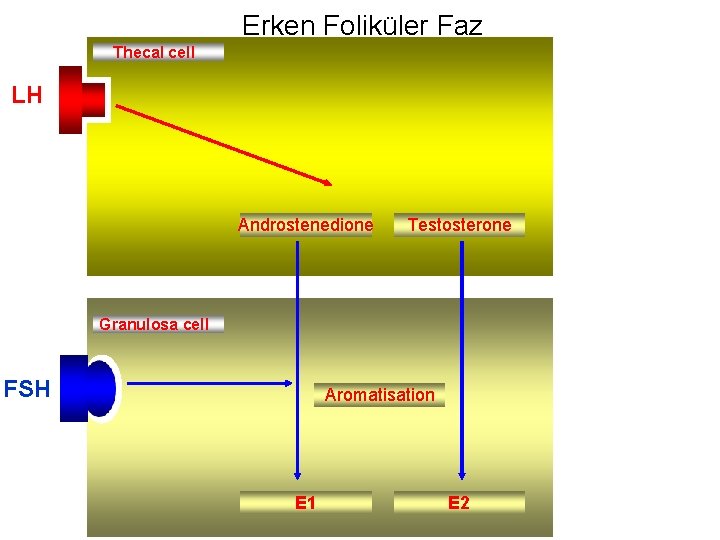

Erken Foliküler Faz Thecal cell LH Androstenedione Testosterone Granulosa cell FSH IGF II Aromatisation E 1 E 2